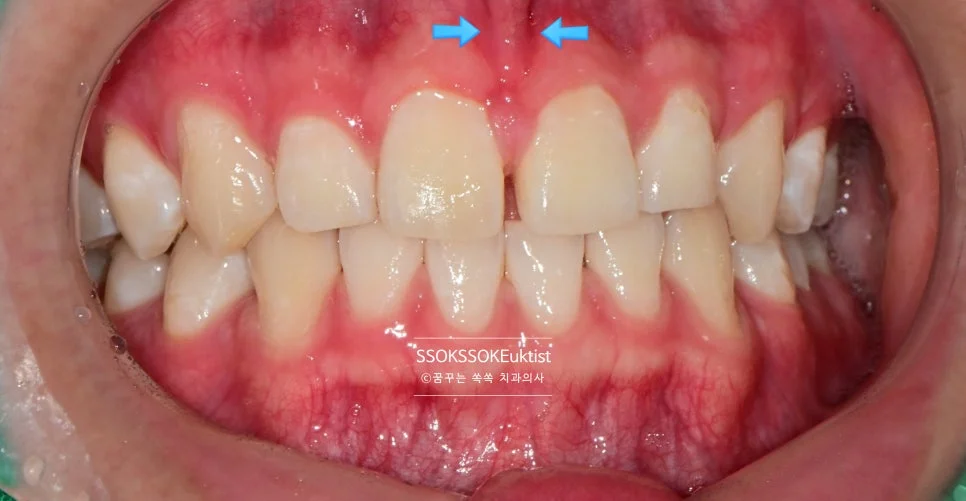

원인 2. 순소대의 과도한 발달

간혹 위 앞니 가운데에만 치아가 벌어진 경우도 있는데요,

순소대가 과도하게 발달하여 앞니 잇몸 근처까지 연장되어 있는 경우, 대문니 사이만 공간이 닫히지 않고 벌어져 있는 경우가 있습니다.

측면에서 바라본 사진입니다. 생각보다 틈이 커서 한 치아만 치료할 경우 한 개 치아만 너무 커 보이는 게 될 것 같아, 양쪽 치아 모두 레진으로 치료하는 것이 좋습니다.